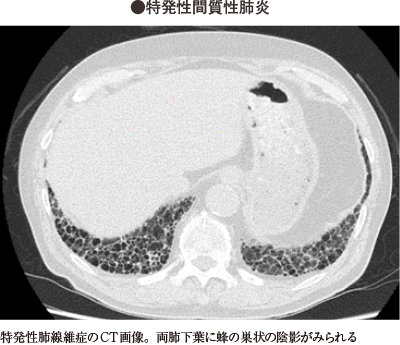

【裁断済み】「症例から学ぶ 間質性肺炎の臨床・画像・病理」田口善夫 / 野間惠之 / ⼩橋陽⼀郎 / 岡輝明定価: ¥ 12000#田口善夫 #野間惠之 #⼩橋陽⼀郎 #岡輝明 #内科 #外来 #内科専門医 #救急・集中治療 #当直 #内科 #レジデント #画像検査 #手技 #臨床 #救急 #研修医 #医学書 #医書 #医師 #薬物治療 #診察 #診療 #レジテントノート #病院 #医学 #本 #自然/医療・薬学・健康本文に書き込みなし。素人検品、素人保管です。ローラー痕や、上下面、ページ端に汚れなどがある場合があり、ご容赦願います。あくまで中古品のため、神経質な方はご遠慮ください。